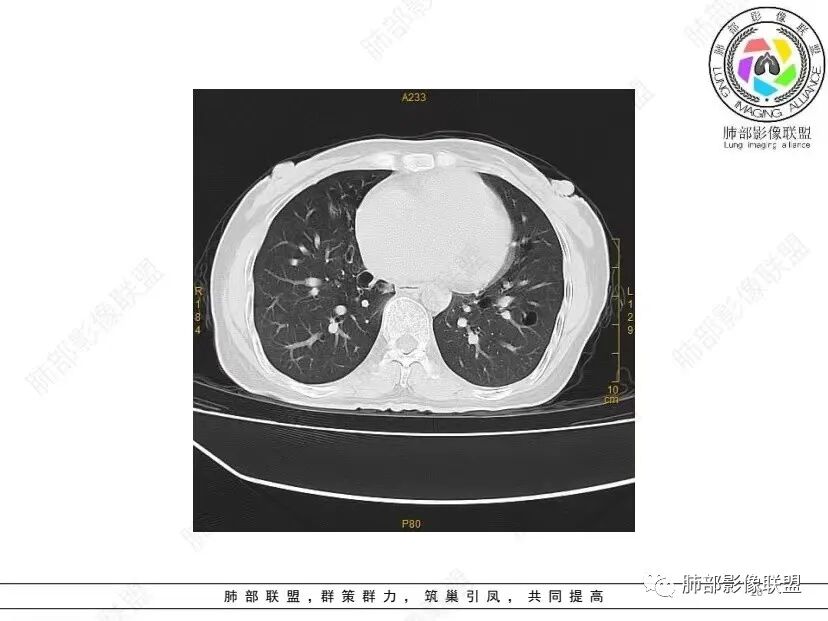

秦化君: 晨读 双肺不均匀散在多发囊状影,大小不等,部分囊形态欠规整,壁薄均匀,部分囊胸膜下平行。双肺少许斑片状磨玻璃影,边缘模糊。考虑BHD综合征。鉴别PCP,LIP。

红日初升: 中年女性,双肺多发气囊,背景干净,大小不一,下肺韧带旁较大,考虑BHD,鉴别LIP、LAM

宇宙: 中年女性,两肺多发大小不等薄壁囊状影,两肺纵膈胸膜下分布明显,考虑BHD,鉴别LAM

良孑: 两肺多发含气囊腔,大小不等,囊周见血管伴行,首选BHD,建议查双肾情况,鉴别Lam

这个病例目前影像特点,多囊,囊主要位于下肺,胸膜下及小叶核心为主

伴随少许索条,而且这些病灶与囊不一定有相关性

囊的分布,PLCH基本可以排除

囊壁薄且均匀,光滑,形态规则,基本除外恶性

单纯囊,无斑片及其他实性病灶,感染不支持,可能的是:LAM、BHD、LIP

从囊的分布、大小,BHD可能性可能大一些,但是LIP、LAM都可以这样表现,具体诊断应该是这三种之一,影像缩小到这里我觉得就差不多了,结合临床考虑就行,不支持靠影像强下结论。

临床诊断BHD综合征需要满足一个主要或两个次要标准。主要标准包括:1、皮肤上至少发现5个纤维滤泡瘤,至少1个组织学证实;2、致病的FLCN种系突变阳性。次要标准:1、多发肺囊肿,双侧基底部,有或无自发性气胸;2、肾癌,起病早(<50岁)或多灶性或双侧;3、 BHD综合征一级亲属。BHD主要影像表现特征:1、两肺内肺囊肿:80%以上的BHD患者会出现肺内囊肿,且倾向于基底部近胸膜下分布,特别是纵隔侧肺膜下,囊肿形状不规则、囊肿可大可小,肺内囊肿多毗邻肺下动脉或静脉近端,胸部CT上囊肿分布和特点对诊断有提示意义。2、继发自发性气胸:BHD患者发生气胸风险是正常人的5倍,BHD患者的气胸发生率约为1/4,气胸复发率则高达59%。3、肾肿瘤:(常为双侧性、倾向于嫌色细胞组织学亚型)4、皮肤表现:(为面、颈部纤维性毛囊瘤、毛盘瘤)